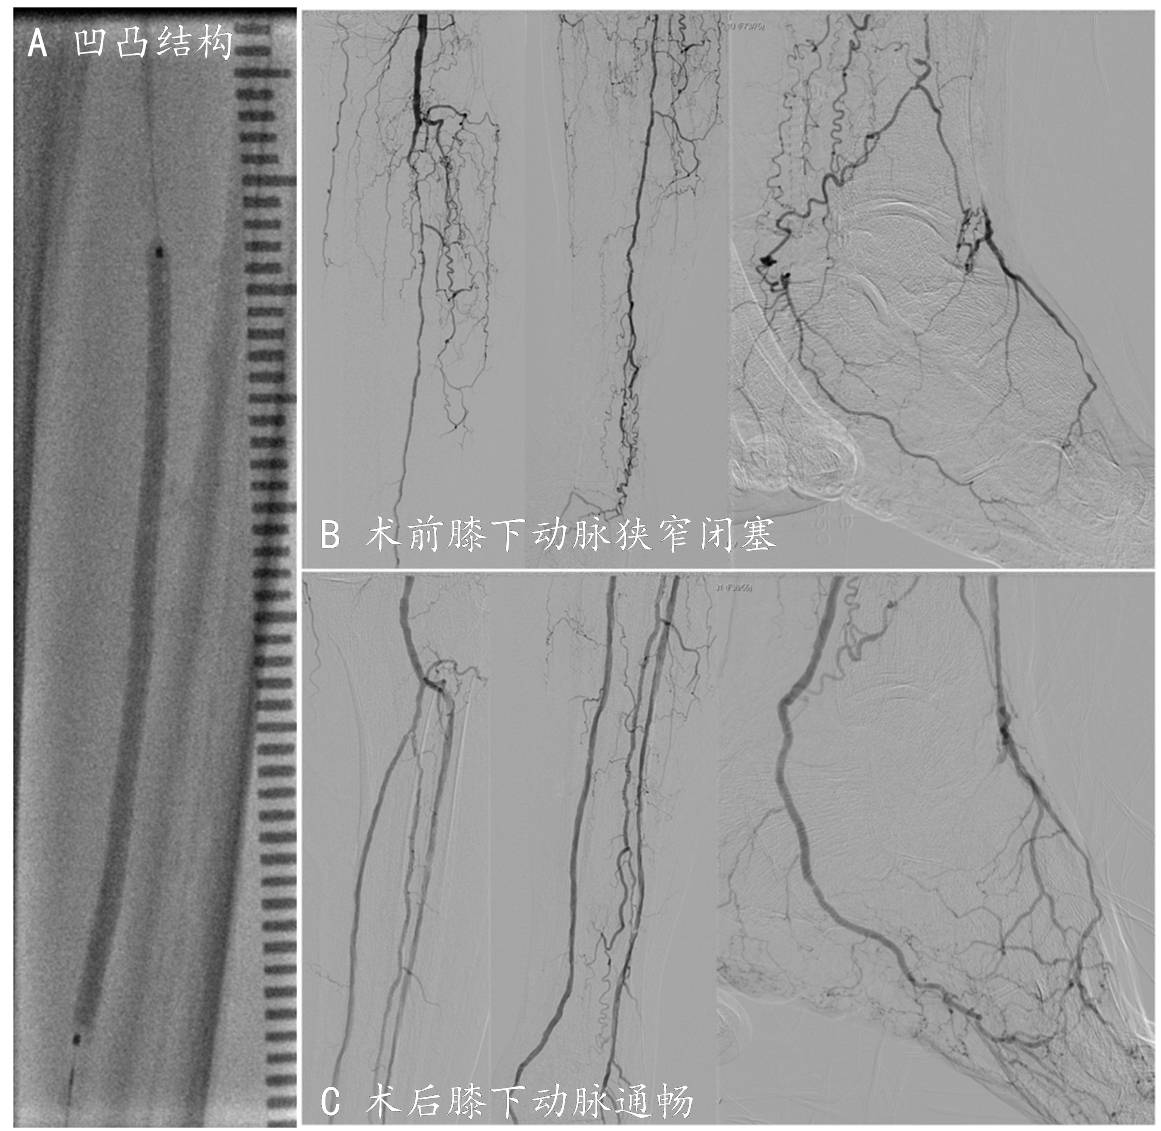

刘女士,86岁,左侧小腿发凉、小腿肚子疼痛持续加重,近期出现静息痛,夜间因为疼痛无法入睡。张童医师在门诊接诊刘女士,通过下肢动脉增强CT检查发现刘女士膝下三条动脉:供血至足背的胫前动脉与供血至足底的胫后动脉完全闭塞,唯一的腓动脉多节段重度狭窄、岌岌可危。这种慢性严重肢体缺血(Chronic Limb-Threatening Ischemia, CLTI)的患者,如果不能及时进行药物治疗或血运重建,2年内因心血管风险造成的死亡比例可达30%,23%以上患者可能出现踝以上大截肢。手术中张童医师以娴熟的技术,由胫前动脉与胫后动脉分别摸索向下的2条导丝在足弓顺利会师,应用2.5mm直径巧克力球囊在3条动脉分别扩张成形,顺利实现了膝下3分支及足弓血运重建。术后刘女士足背与踝后区域均能摸到动脉搏动,足部皮温回暖,夜间可以安然入眠。

图4 巧克力球囊用于膝下动脉闭塞病变血管扩张成形

A巧克力球囊扩张3支动脉,可见凹凸结构

B术前膝下动脉狭窄闭塞

C术后膝下动脉血流通畅